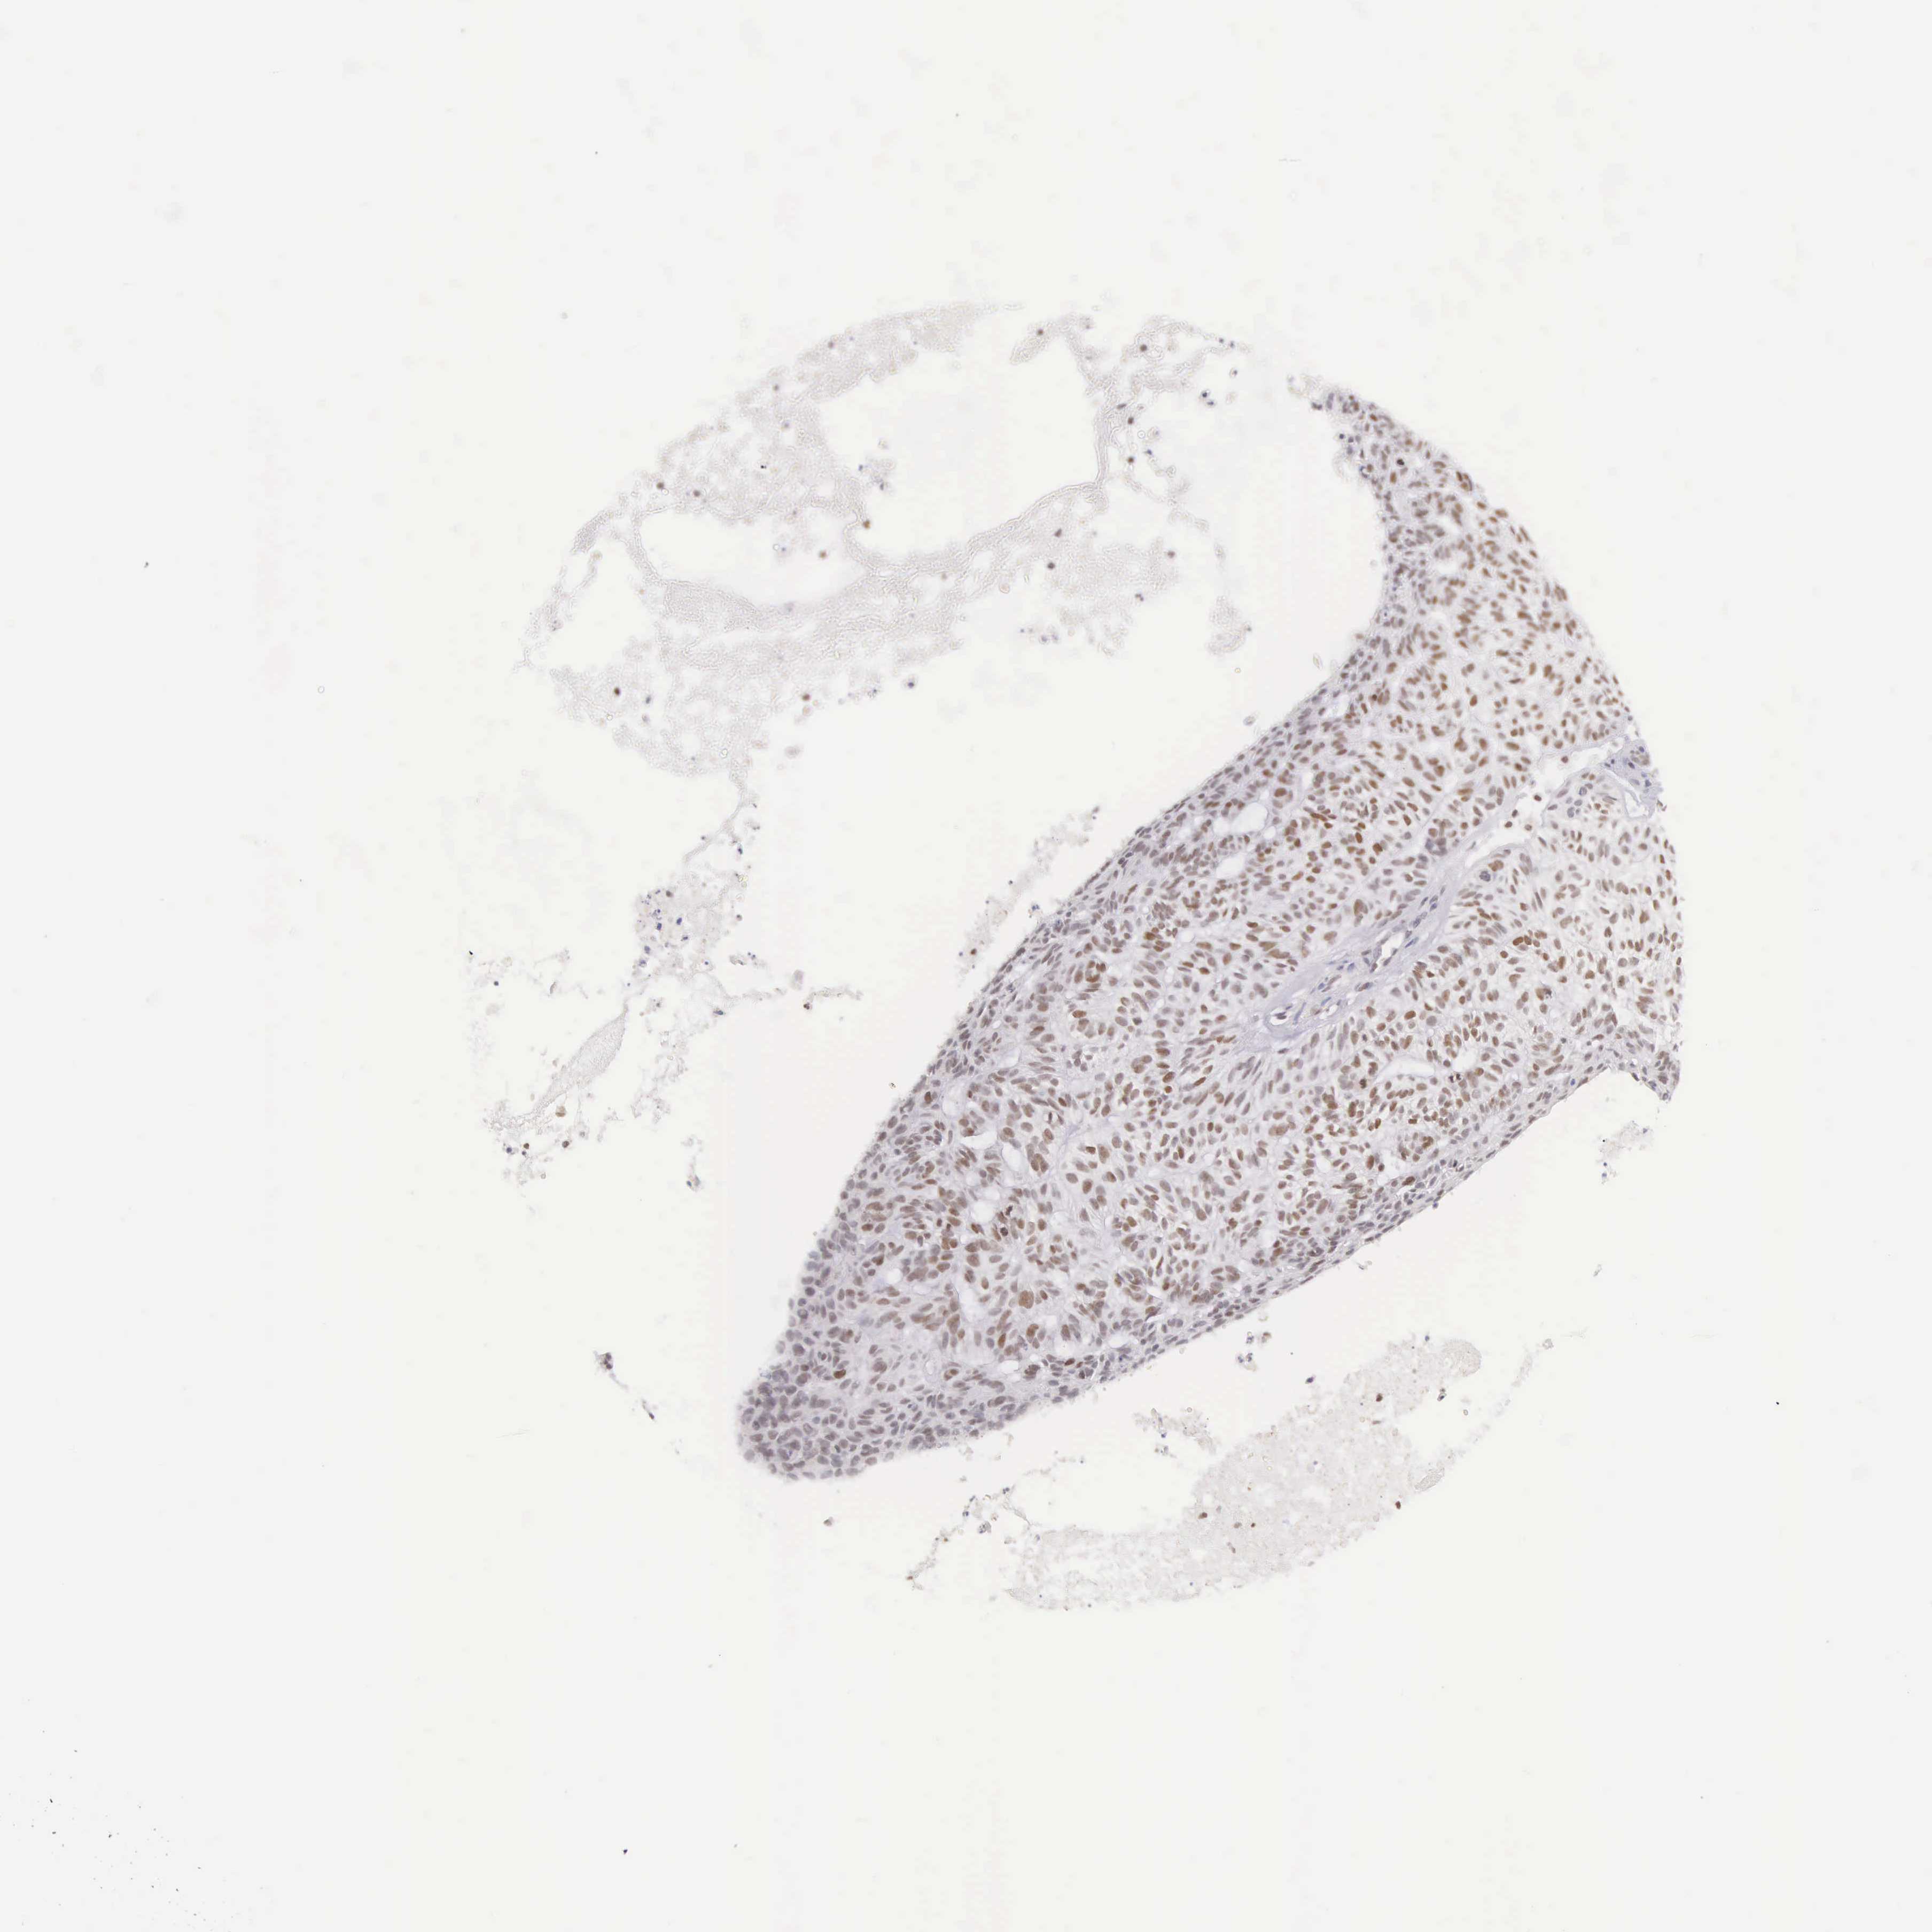

Basal cell and squamous cell cancer

SKIN CANCER - Protein expressioni

A mouse-over function shows sample information and annotation data. Click on an image to view it in a full screen mode. Samples can be filtered based on level of antibody staining by selecting one or several of the following categories: high, medium, low and not detected. The assay and annotation is described here.

Each image is clickable and will lead to virtual microscopy that enables deeper exploration of all samples and also displays staining intensity scores, fraction scores and subcellular localization as well as patient and tissue information for each sample.

Antibody HPA000660

Squamous cell carcinoma, NOS